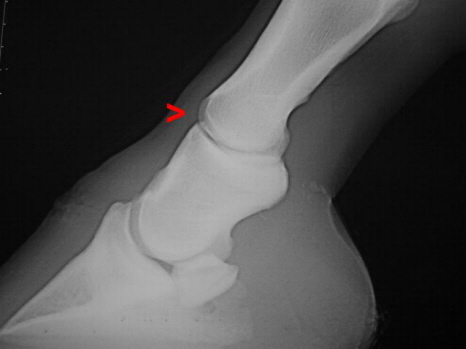

Subluxation Krongelenk